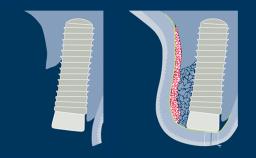

Sinus floor elevation is a predictable procedure for vertical bone augmentation in the posterior maxilla that compensates for inadequate bone height. Grafting material is placed into the sinus to increase available bone height and to facilitate the placement of implants of the desired dimensions and in the correct prosthetically driven positions.

Sinus floor elevation can be performed by lateral window or transcrestal approaches.

This module will focus on the surgical treatment concept and steps for the transcrestal sinus floor elevation technique.